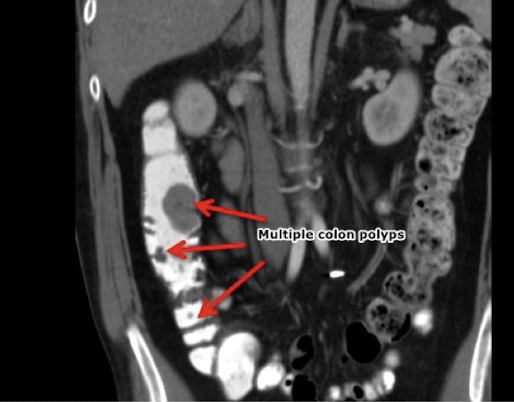

What is this and what type of scan

Colon polyp, CT